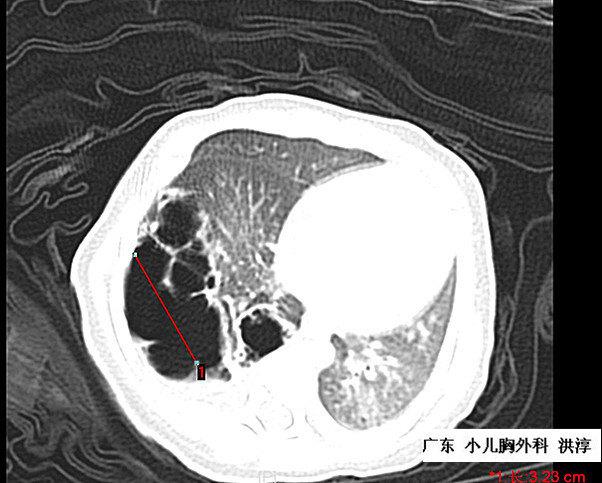

肺囊腺瘤:今天遇到一个罕见病例给大家分享一下!

先天性肺囊腺瘤

小孩肺囊腺瘤,手术不知道国内哪个医院微创